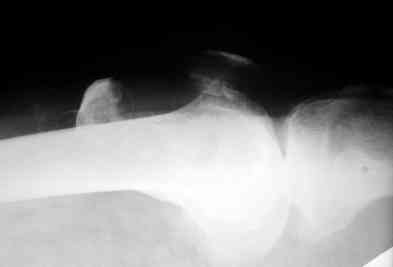

прилагаю снимки надколенника.

po moemu na snimke viden avascul necrosis of talar bone . lechit v cootvetstvii .